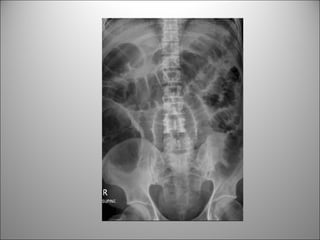

TEJIDO BLANDO

• Visión limitada de estructuras-órganos

• Puede verse +/-

– Hígado

– Bazo

– Riñones

– Psoas

– Vejiga

– Bases pulmonares